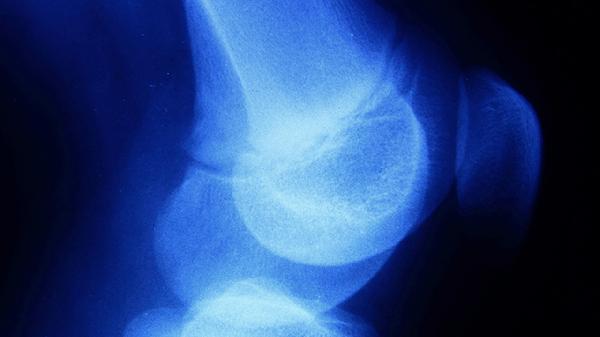

下颌骨缺损修复最常用的骨瓣包括髂骨骨瓣、腓骨骨瓣、肩胛骨骨瓣、桡骨骨瓣和肋骨骨瓣。选择骨瓣需综合考虑缺损部位、大小及患者个体情况。